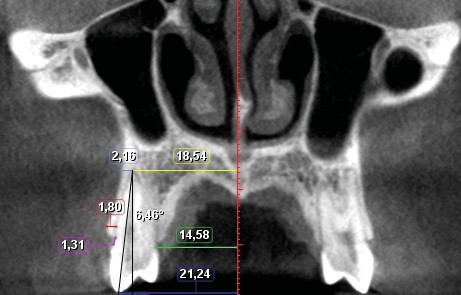

Sept mesures ont été réalisées pour quantifier le déplacement dentaire et les modifications alvéolaires (fig. 1 et 2). de chaque côté : –...